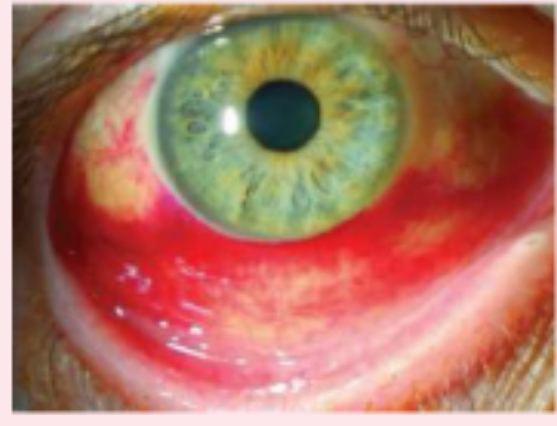

subconjunctival hemorrhage

bright red areas of the sclera